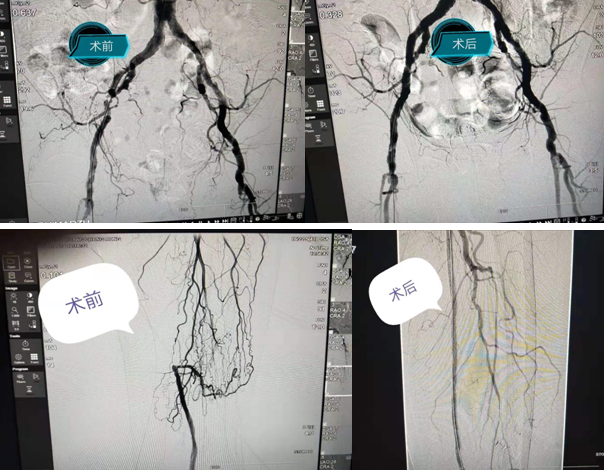

7月22日,市内猛降暴雨,阻塞了众多交通要塞,唐博副教授却毅然选择风雨兼程,赶赴秀山,抵达县医院已经是深夜11点半了。经过短暂休息后,唐博副教授一大早就来到县医院,参加科室交班晨会,开展教学查房、示范查体,并与患者家属充分沟通病情;陈运清副院长组织开展术前讨论,围绕术前准备、术中手术方案和术中、术后的并发症防治及流程等方面进行了精心安排。在唐博副教授的带领下,历经3.5小时,成功开通闭塞病变的血管,并对右侧股浅动脉闭塞病变进行了造影。由于病情复杂,黄大爷还需要在1个月以后再进行二次手术。

在重医附二院专家团队指导下,帮助秀山分院首次成功开展了下肢闭塞血管开通手术,为患者解决病痛,同时也体现出重医附二院医联体内部的紧密性与高效性。真正做到了让偏远山区百姓足不出户,就能享受到三甲医院专家的优质医疗服务,为提高当地百姓幸福感、提升医联体成员单位综合服务能力发挥着积极的促进作用!